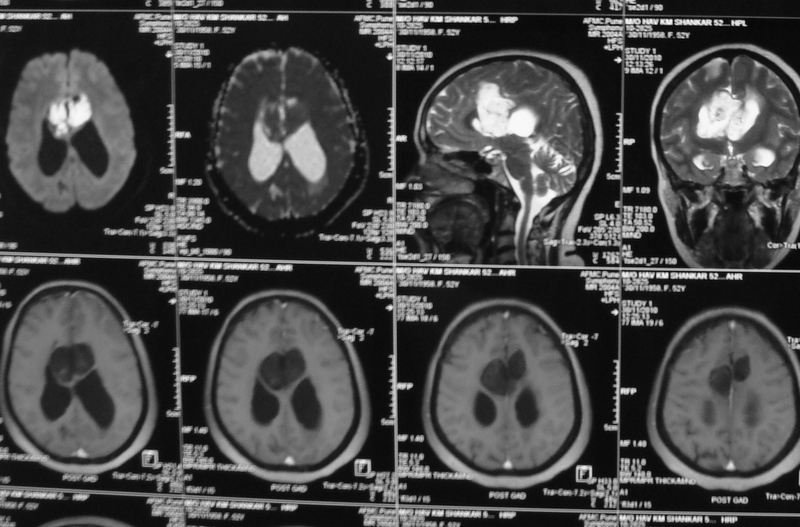

Medulloblastomas

Medulloblastomas are common tumors in childhood, often presenting with vomiting and headache. These tumors are located in midline of the cerebellum (back of the head). Diagnosis is made with MRI, and complete excision can be done safely in majority of the children.